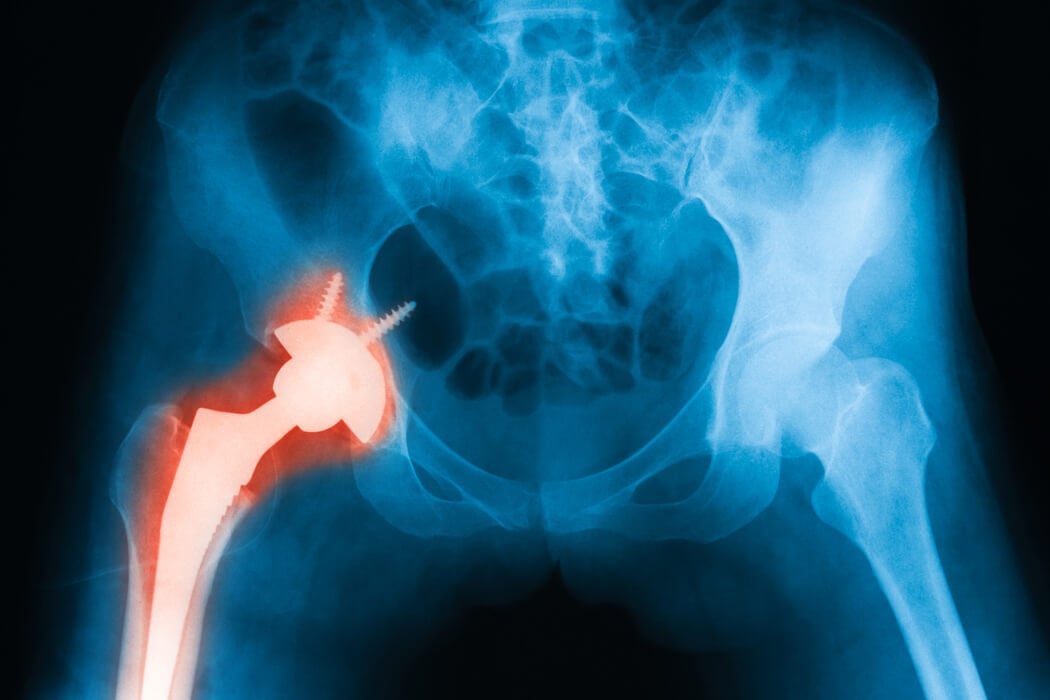

A defective medical device is any piece of medical equipment that does not function properly due to either poor manufacturing practices or materials. Poorly manufactured devices, or those that were made with inferior materials, can cause extensive tissue damage requiring multiple surgeries to ensure the necessary repairs In some cases, the device may not work properly due to the type of procedure used to implant it into your body.

- Hip, knee, or shoulder joint replacements